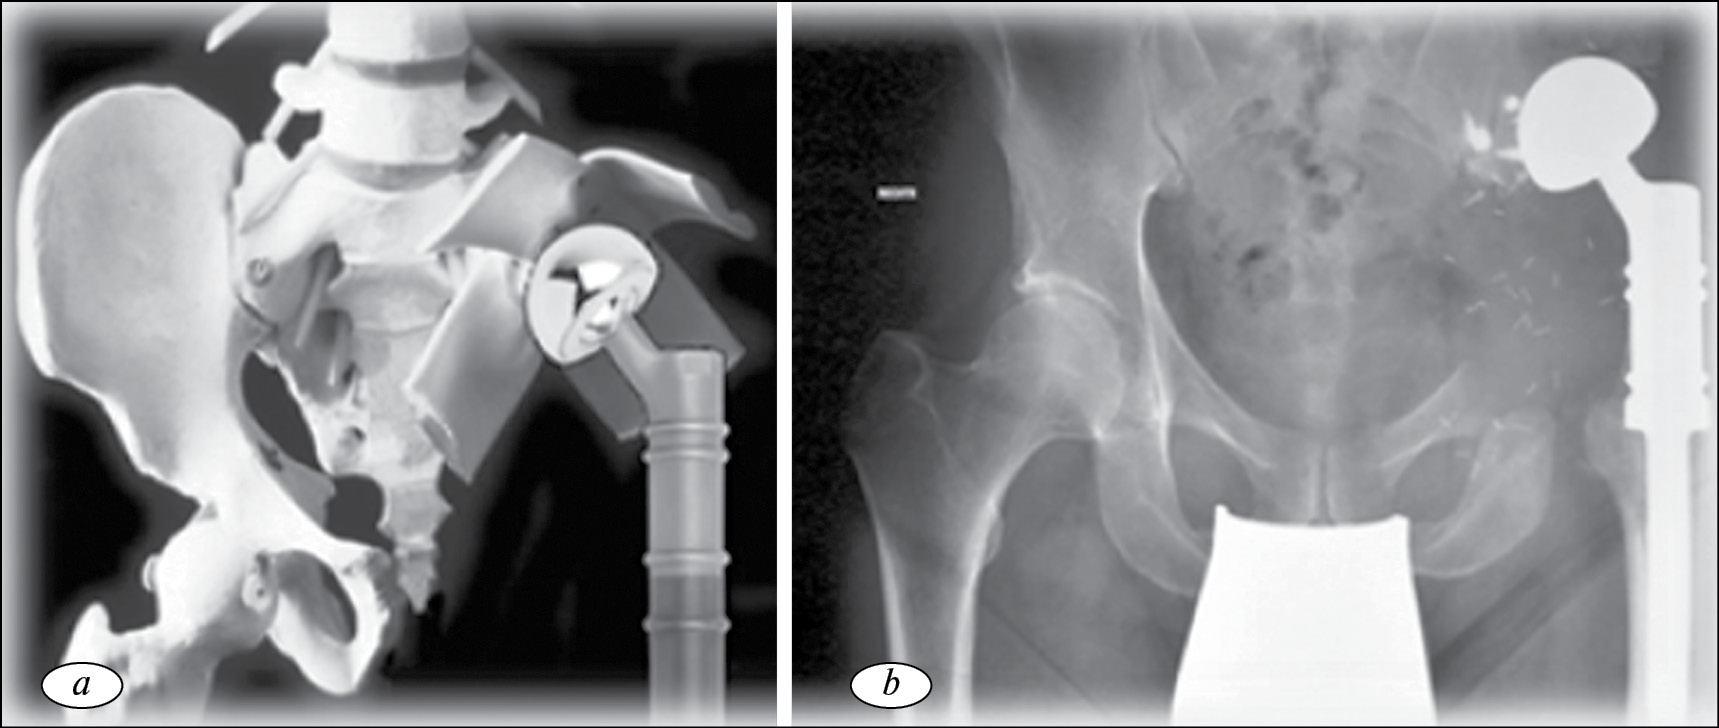

Реконструктивная онкологическая хирургия тазового кольца берет свое начало с 70-х годов прошлого века, когда J.T. Johnson выполнил двум пациентам с хондросаркомой параацетабулярной области реконструкцию вертлужной впадины после удаления опухоли путем проведения через оставшиеся лонную и подвздошную кости нескольких стержней и спиц, к которым при помощи костного цемента фиксировал чашку эндопротеза тазобедренного сустава (рис. 1).

Рис. 1. Рентгенограмма костей таза, реконструкция выполнена при помощи комбинации титановых стержней, костного цемента и эндопротеза тазобедренного сустава [39]

Первый пациент был жив через 5 лет после операции без данных о прогрессировании, мог ходить без средств дополнительной опоры. Второй пациент передвигался самостоятельно при помощи трости, однако через год после лечения у него выявлен рецидив опухоли, в связи с чем было рекомендовано выполнить МПБВ, от которого пациент отказался [15, 18].